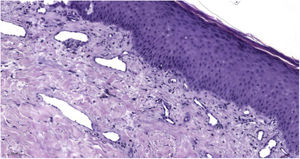

Paciente masculino de 57 años fue remitido a la consulta de Dermatología para la valoración de una placa esclerodermiforme hiperpigmentada de 30 × 20 cm, con una úlcera exudativa de bordes indurados rodeada de un área eritematosa mal delimitada, localizada en la región lumbar y de cinco meses de evolución (fig. 1). El paciente tenía antecedentes personales de diabetes mellitus tipo II, hipertensión arterial y había sido diagnosticado recientemente de un mielolipoma. Este fue tratado mediante una embolización supraselectiva de la arteria frénica derecha, la arteria suprarrenal derecha y la arteria lumbar L2 seis meses antes de la consulta. El paciente refería haber comenzado con prurito y un enrojecimiento en la región dorsolumbar unos 15 días después de la intervención mencionada y, desde entonces, la lesión aumentó de tamaño progresivamente y se ulceró. El estudio histológico solo mostró unas dilataciones linfáticas atribuidas a la irradiación (fig. 2).